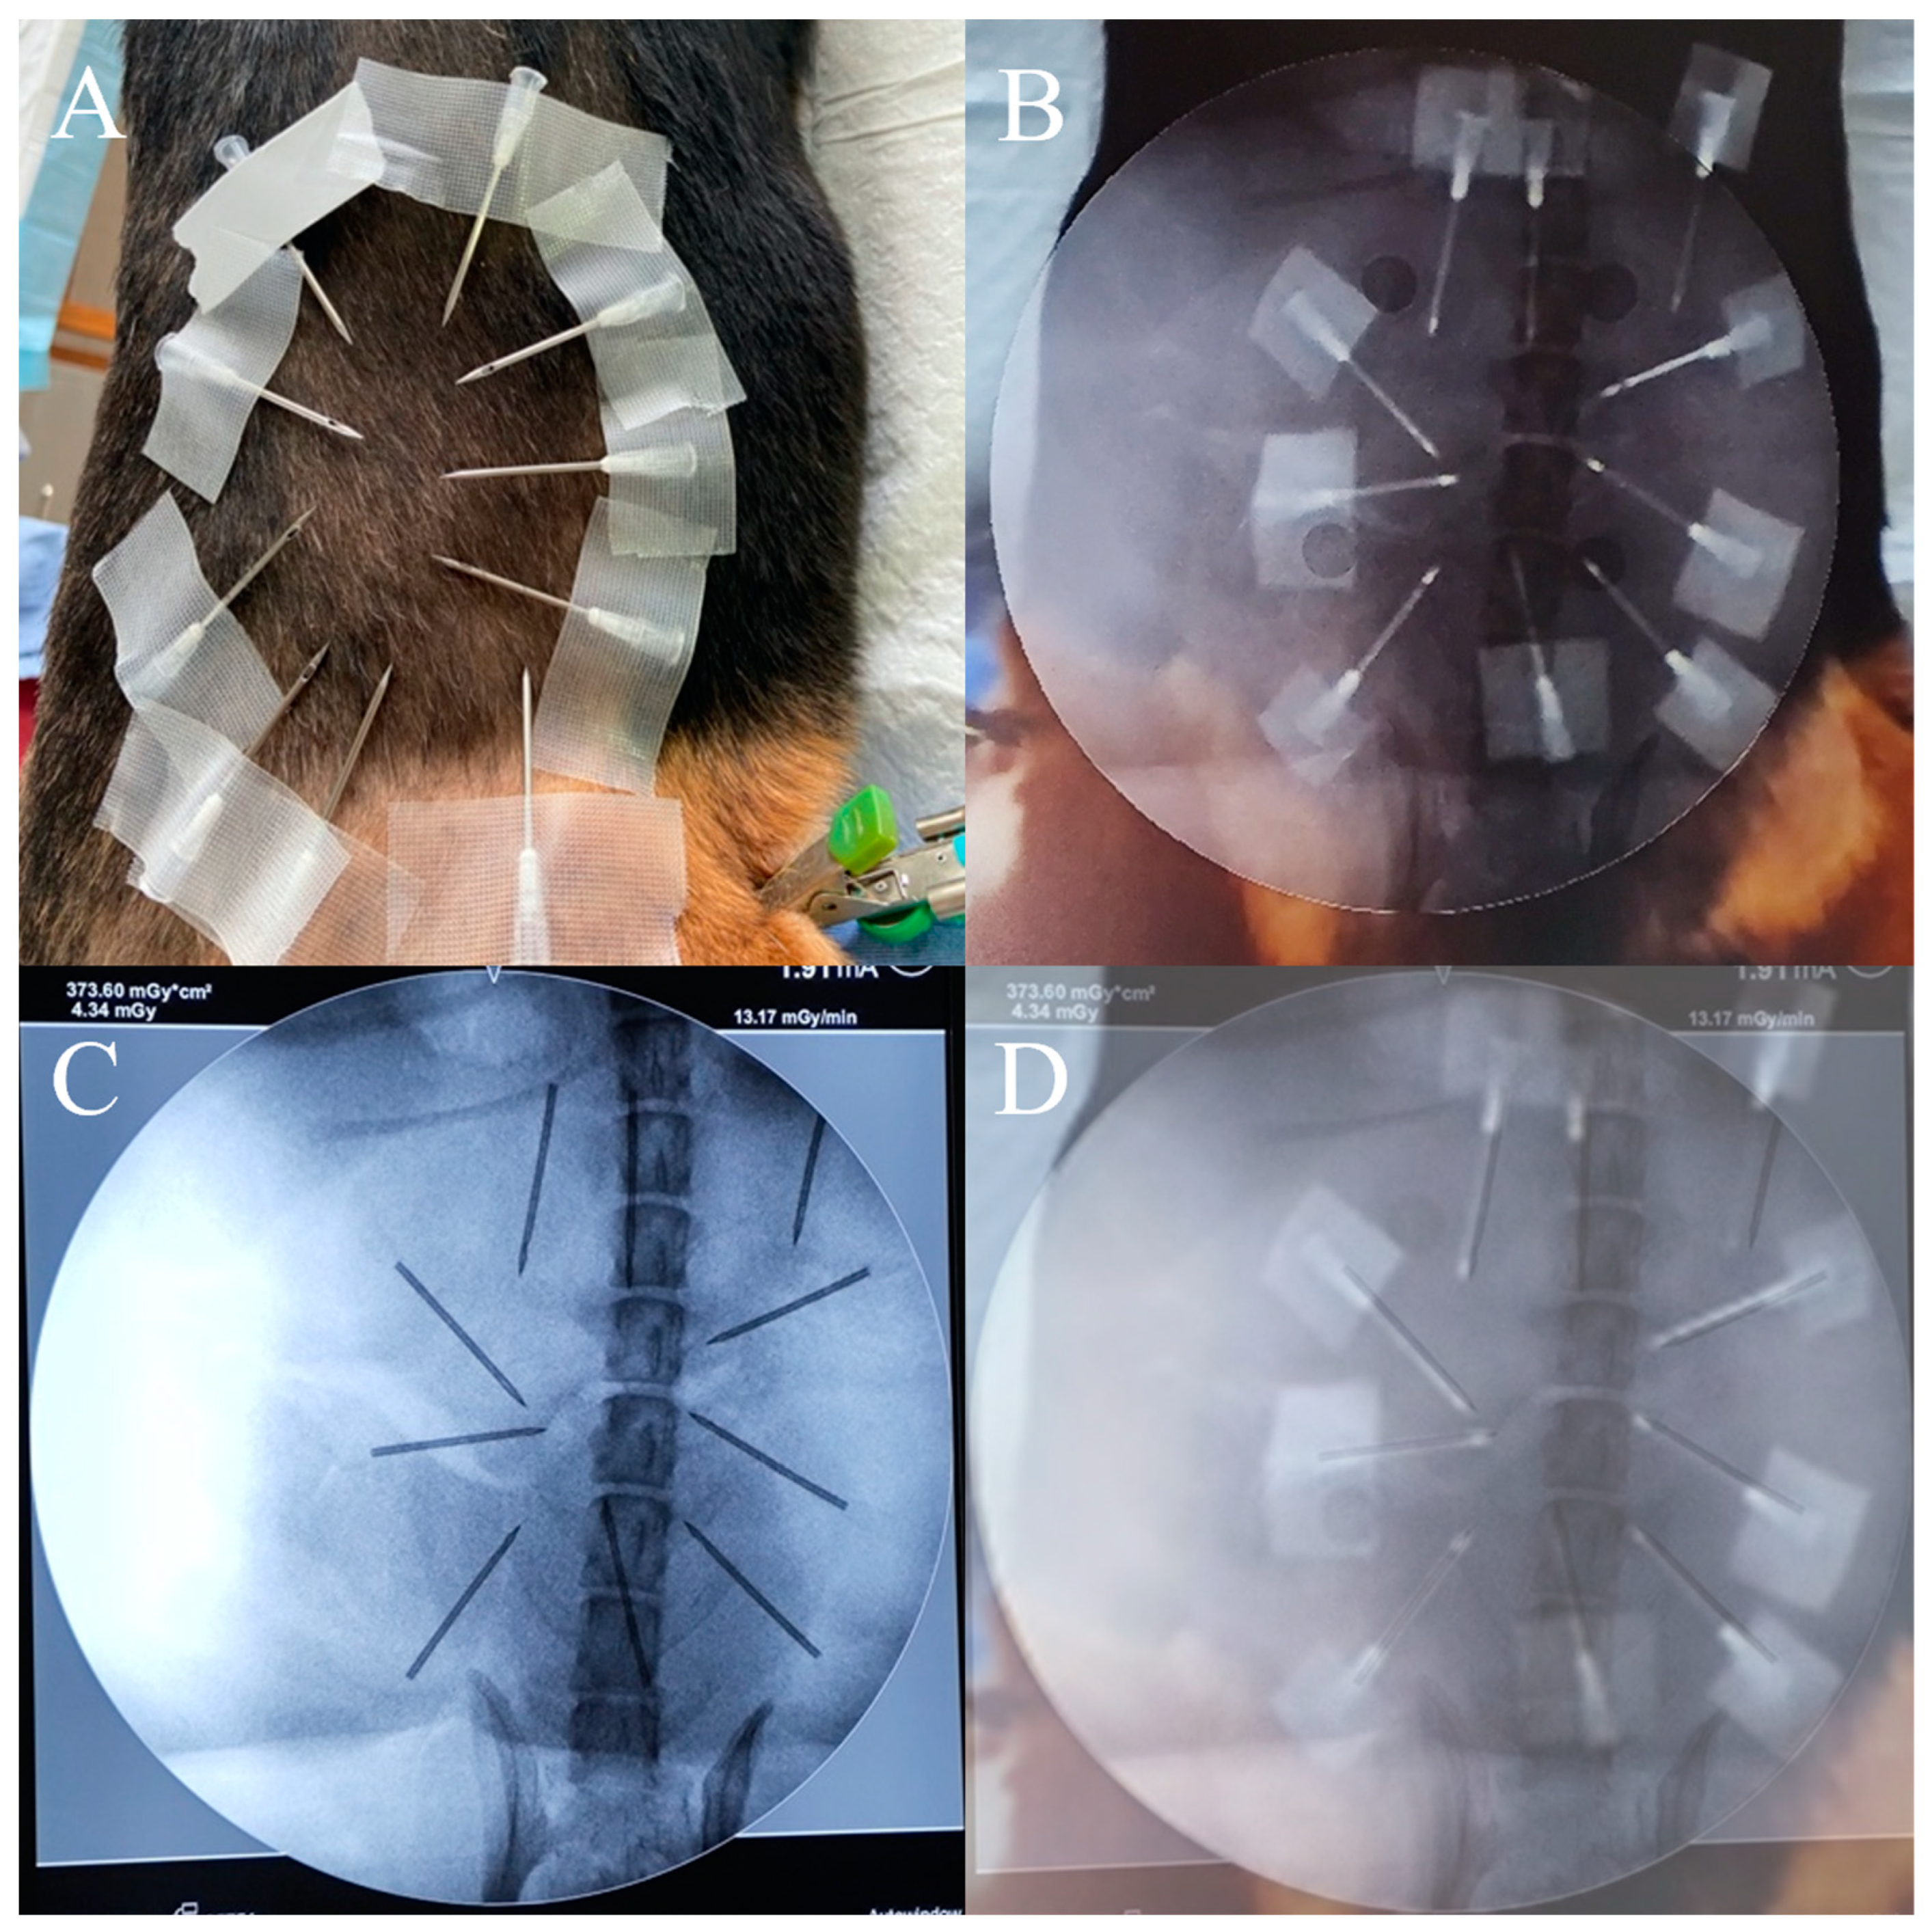

A screenshot was taken, and the final positions of the AR needle in the AR radiographs were recorded. Then, the real radiographs were taken, and the final positions of the real needle in the real radiographs were recorded (Figure 7). The positions of the AR needle and the real needle were compared. The needle tip distance error and angle error were evaluated. A total of 20 experiments were performed.

The puncture process was finally guided by the AR-MISS system. The results showed that the position of the AR puncture needle in the AR radiograph was similar to the position of the real puncture needle in the real radiograph (Figure 7). The AR-guided puncture distance error distribution diagram and angle error distribution diagram are shown in Figure 10. The AP puncture average distance error was 2.47 ± 0.86 mm, the lateral puncture average distance error was 2.85 ± 1.17 mm, the AP puncture average angle error was 0.87 ± 0.78°, and the lateral puncture average angle error average angle error was 3.54 ± 2.82°. In the experiment, no massive bleeding, nerve injury, or other adverse events were observed.

Figure 7. AR navigation guided puncture. (A,B) The position of the AR needle in the AR radiograph shown in the video; (C,D) the position of the real needle in the real radiograph shown in the C-arm. (A,C) Anteroposterior view; (B,D) lateral view.